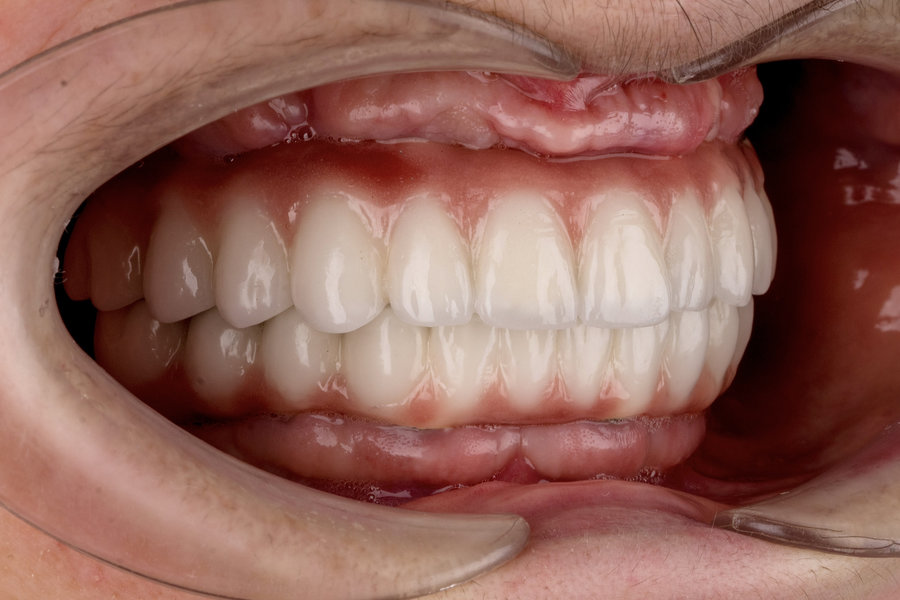

Cazuri clinice conceptul All-on-6